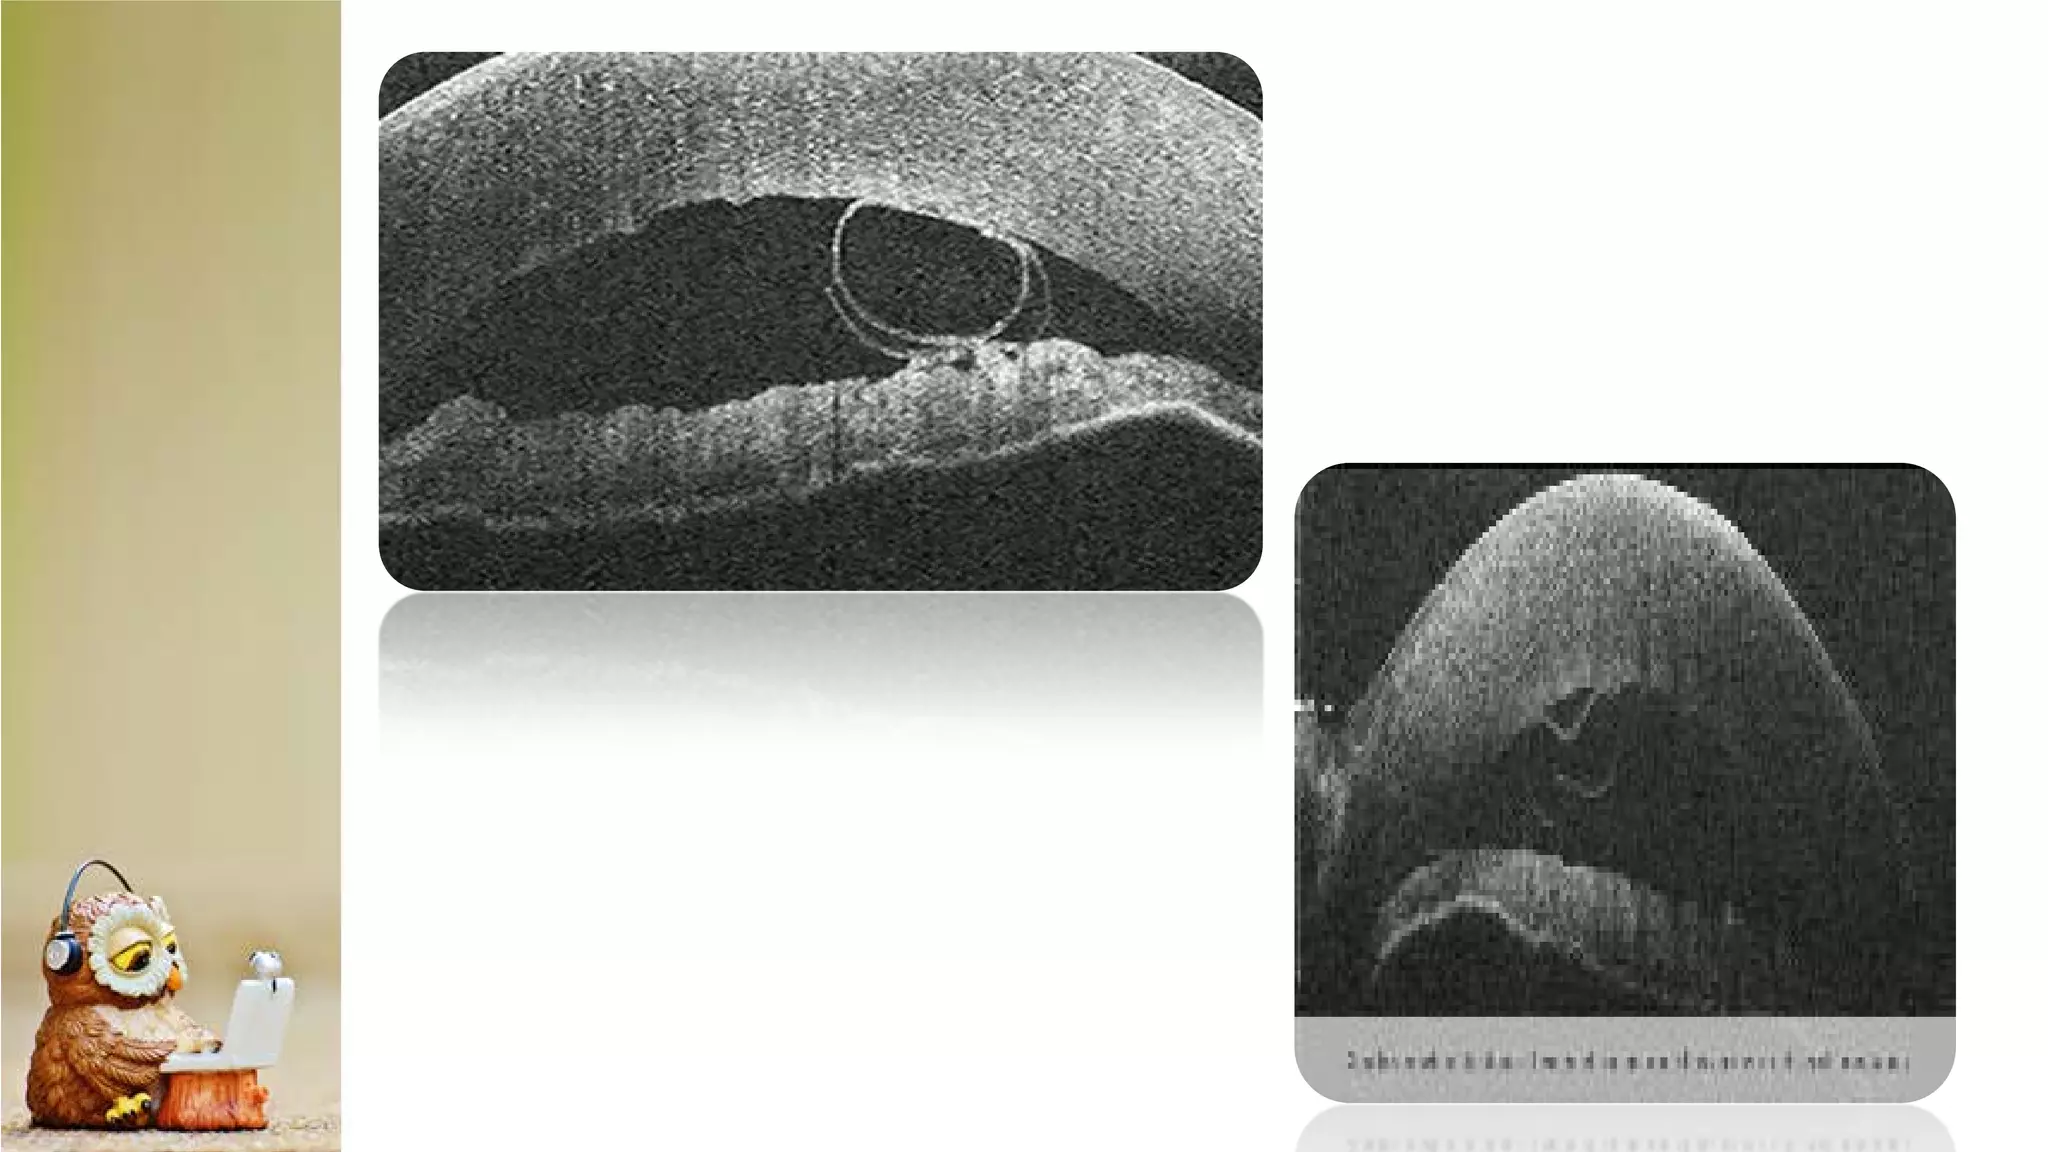

The document discusses Anterior Segment Optical Coherence Tomography (AS-OCT) as a noninvasive diagnostic tool providing high-resolution cross-sectional images of the ocular surface and anterior segment. It details various OCT devices, their manufacturers, measurement types, and scanning speeds, highlighting qualitative and quantitative assessment capabilities. The document also notes limitations such as resolution modes and specific ocular conditions that may affect results.